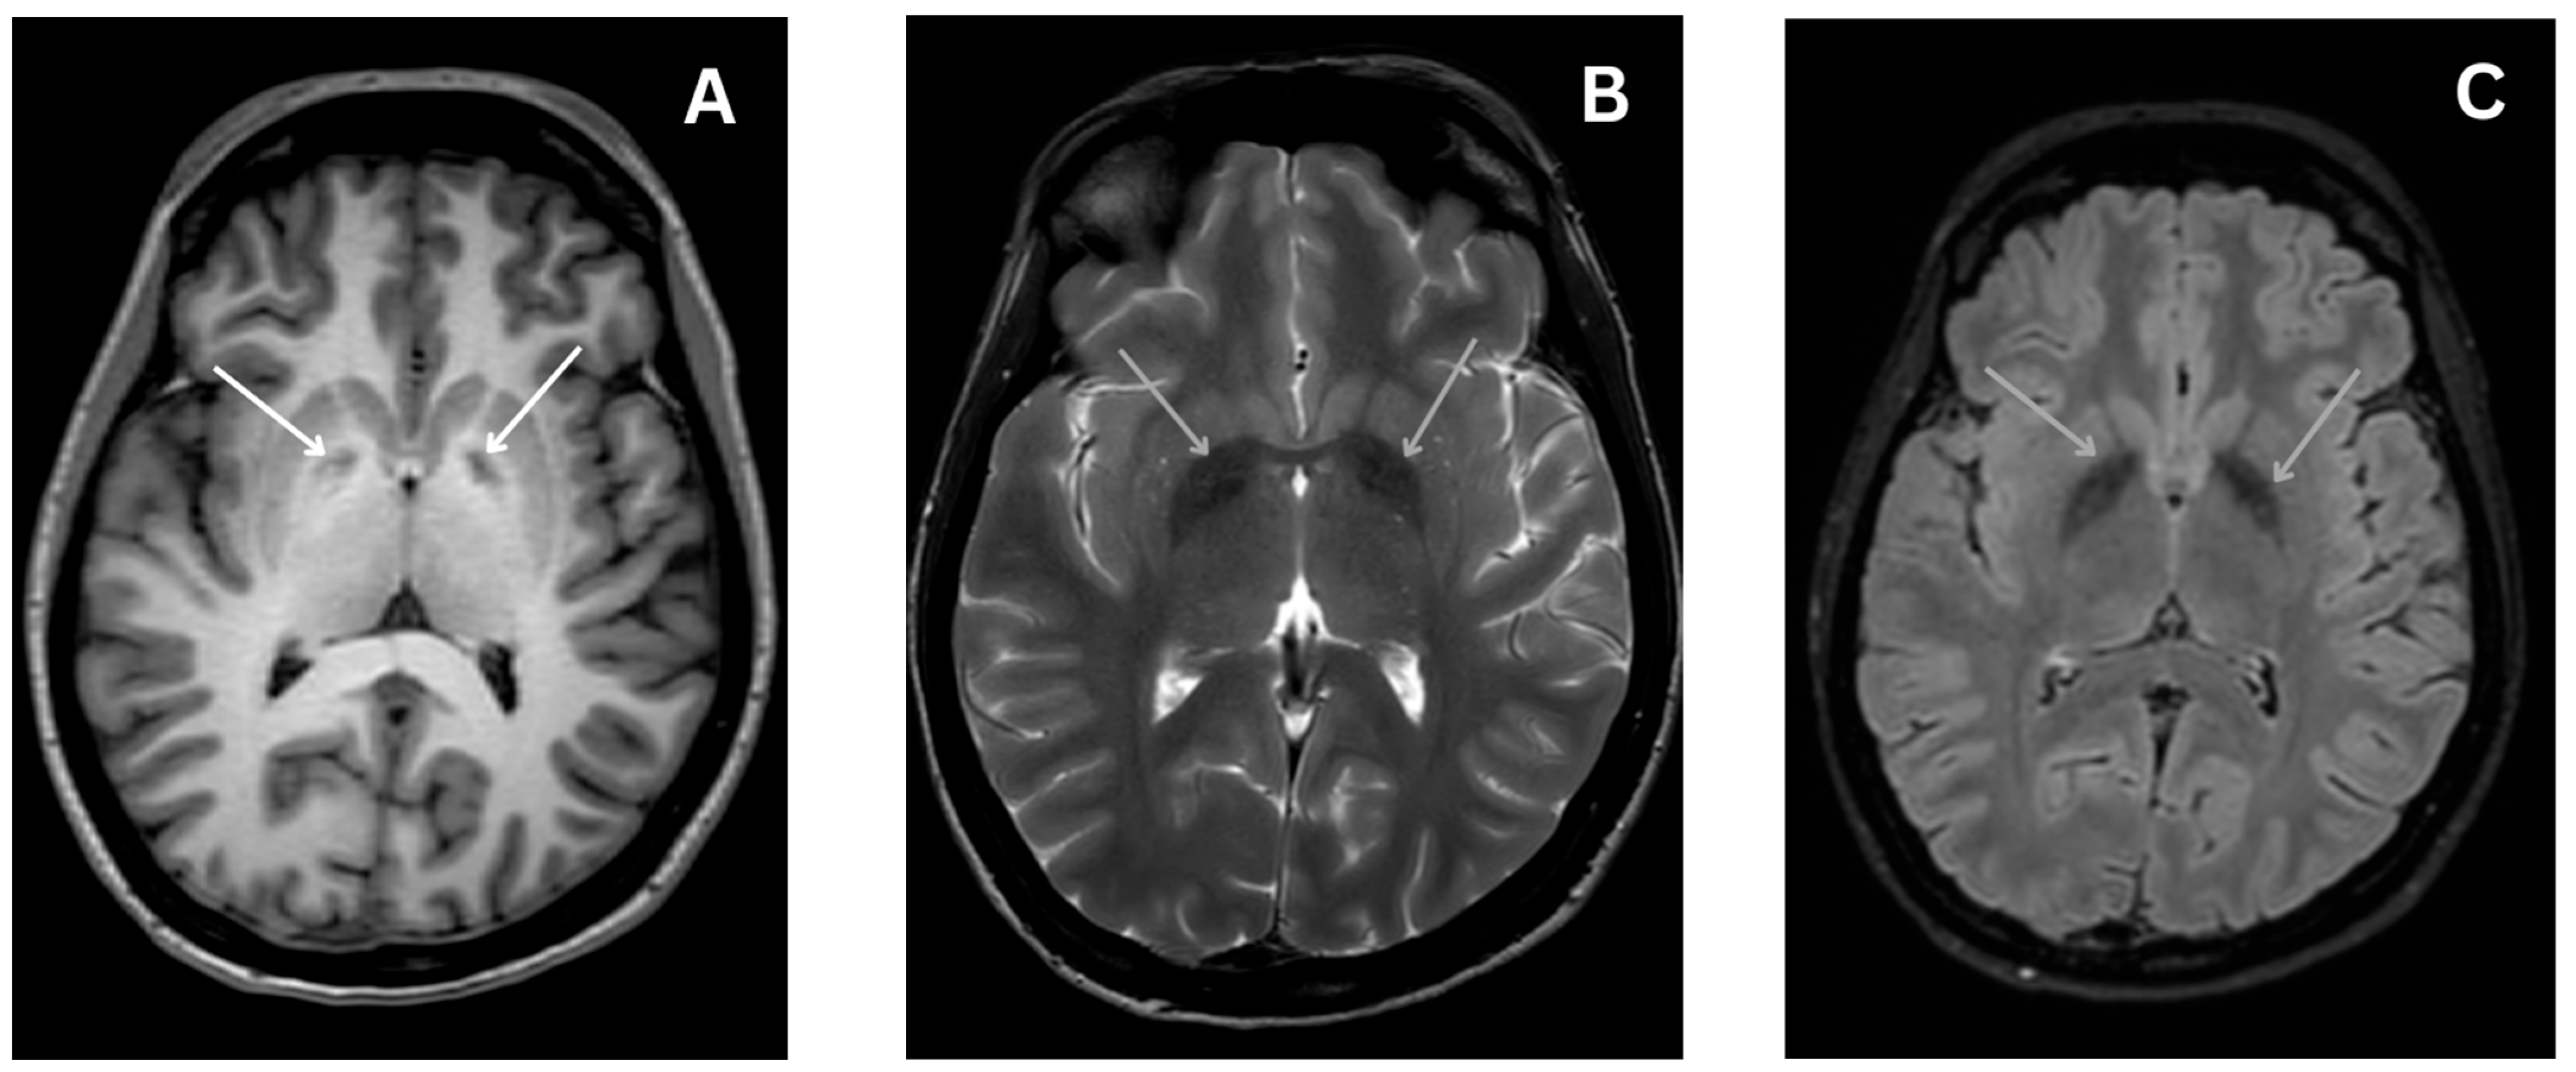

4.4.4. Magnetic Resonance Imaging